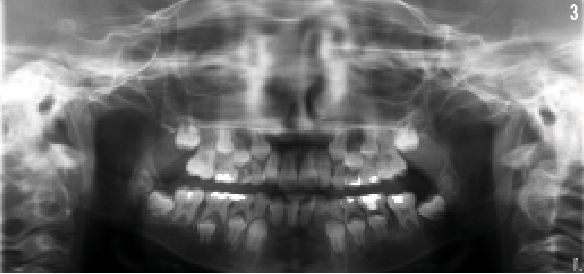

A 15-year-old girl presented with diarrhea, abdominal pain, and hematochezia. Her past medical history was significant for pulmonary fibrosis, aplastic anemia that required a bone marrow transplant at the age of 3 years, and nail dystrophy and leukoplakia at the age of 5 years (Figures 1 and 2). She also had dental anomalies that consisted of teeth with short roots and a history of developing multiple dental caries requiring numerous restorations (Figure 3).

A day before discharge, the girl underwent a bone marrow biopsy and transjugular liver biopsy with hepatic venous wedge pressure measurements. The results of the liver biopsy showed differential hepatic venous pressure of 9 mmHg, which signified mild portal hypertension. Liver biopsy results also revealed histologic findings consistent with extensive hepatic fibrosis and early cirrhosis (Figure 4). Bone marrow biopsy results showed hypocellularity and 100% donor engraftment; further evaluation revealed negative results for viral causes of bone marrow failure. When the patient was assessed 2 weeks after the initial evaluation, her levels of liver transaminases were within reference range.